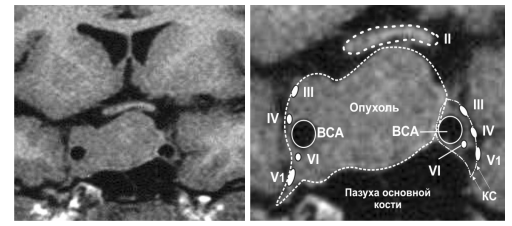

Естественно, что при внедрении опухоли в полость кавернозного синуса нормальная анатомия изменяется. Чаще всего аденомы гипофиза проникают в просвет кавернозного синуса через его медиальную стенку. Заполнив полость синуса, опухоль может распространяться за его пределы через щелевидные отверстия, которые являются естественными входными путями для глазодвигательного, блокового и отводящего черепных нервов. При этом аденомы гипофиза в процессе роста в полость синуса чаще всего вызывают смещение внутренней сонной артерии, глазодвигательного нерва и блокового нерва вверх и кнаружи, а отводящий нерв вместе с первой ветвью тройничного нерва — латерально и книзу. Внутренняя сонная артерия может быть смещена опухолью как к латеральной стенке кавернозного синуса (более удобный вариант), так и к средней линии — медиально (рис. 6).

Рис. 6. Схема пространственного расположения хиазмы, внутренних сонных артерий и нервов, проходящих в кавернозном синусе с эндо-супралатероселлярной аденомой гипофиза

Второй вариант менее благоприятен. До последнего времени медиальное смещение сонной артерии вообще рассматривалось как противопоказание для проведения траснсфеноидального удаления опухоли.

Однако использование эндоскопа позволяет проводить операции даже при самом неудобном варианте смещения сонной артерии.